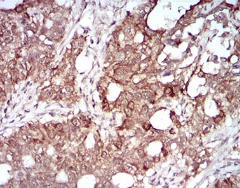

IHC    1/200 - 1/1000